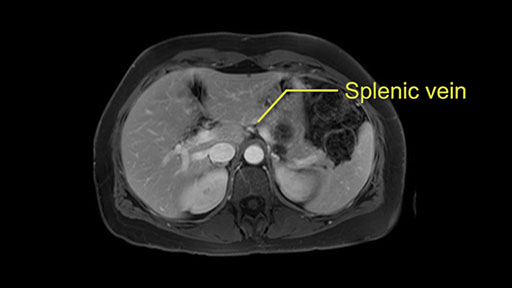

Tumor proximity to splenic vein

Other slowing down moments with this procedure include dissection of the splenic vein and splenic artery. These are technically challenging moments and important moments where care needs to be taken. Not only to avoid bleeding and injury to the vessels but also to ensure an adequate margin.

The lesion itself is quite adjacent to and abuts the splenic vein and therefore we need to anticipate that these two structures will be intimately related and possibly impossible to separate between the two.

The second slowing down moment or consideration I give to a distal pancreatectomy is the anatomy of the portal vein and the splenic artery. And so I look here and the anatomy is pretty straightforward. The splenic vein comes off normally and runs behind the pancreas and I can see the artery superior to that, again coming off in a normal manner from the celiac axis. So those two things, the portal vein and the splenic artery will be taken normally in this procedure.